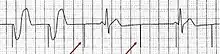

- Inflate the balloon and advance the pacer into the right ventricle.[3] This will appear as pacer spikes and a wide QRS complex on the monitor.[3]

Setup for doing an ECG off the device Example of ECG off the device a) free floating in the RV b) in contact with the RV wall

Example of ECG off the device a) free floating in the RV b) in contact with the RV wall It is possible to place the lead in the coronary sinus, normal (left) dilated (right). Such placement is okay.

- Failure to capture

This results in a pacemaker spike without a QRS complex.[2] The solution is often to turn up the current (mA).[2] Other measures include checking for electrolyte abnormalities, rolling the person a different position, and repositioning the device.[2]